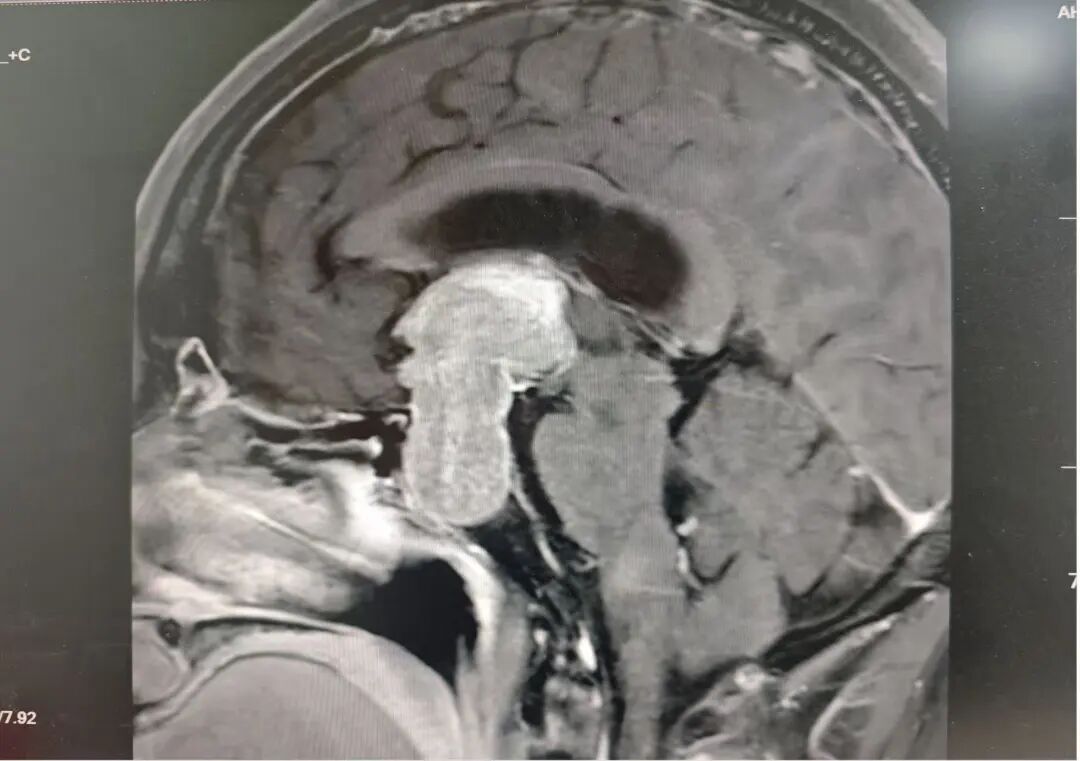

“看东西越来越模糊,连报纸上的字都快看不清了,头也痛.....”55 岁的王先生(化名)怎么也没想到,这几天的不适,竟是因为脑中藏了一颗压迫视神经的巨大垂体瘤。

持续几天的视线模糊,严重影响了王先生的日常生活。为了尽快解决这个问题,他急忙赶到皖北煤电集团总医院东区——宿州心脑血管病医院就诊(以下简称“宿州心脑血管病医院”)神经外科三病区就诊。

神经外科三病区陆路副主任医师接诊后立即为王先生完善了相关检查,检查显示王先生的鞍区占位体积巨大,鞍区垂体瘤。这也是导致王先生头痛,视线模糊的罪魁祸首。

“患者颅内占位体积很大,需要尽快进行手术!”陆主任在与家属沟通时表示。